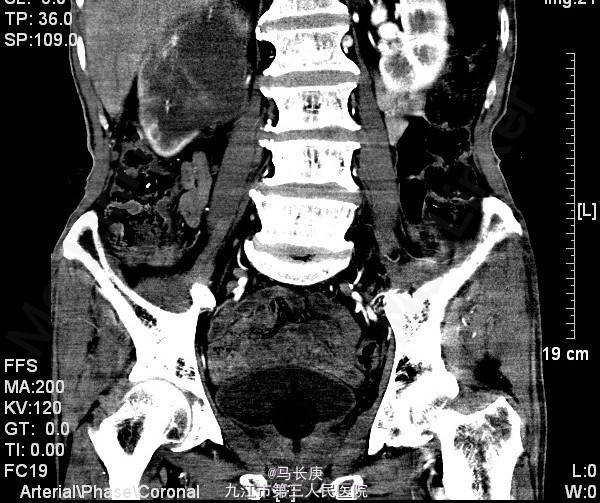

3、查体:无明显异常 4、辅助检查:当地人民医院泌尿系CT平扫+增强:1.右侧输尿管结石2.右肾占位?(未见报告),我科fish(+)CTU:肾盂癌,侵蚀右肾包膜,左肾囊肿,慢性胆囊炎。双肾核素扫描:右肾GFR:9.5,左肾48.5

5、考虑右肾盂癌 6、入院后给予双肾核素扫描、CTU检查,考虑右肾盂癌,给予抗炎、补液、治疗。现病情平稳。 术前诊断:右肾盂癌、胆囊炎、左肾囊肿、右侧输尿管结石、贫血、低蛋白血症、胆囊炎,后行右肾癌根治术,手术顺利,术后恢复较好,术后病理示:肾恶性肿瘤(高分化肉瘤)。